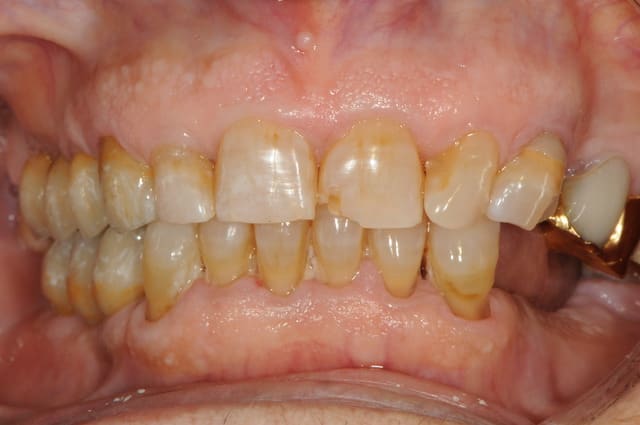

charlie est un blanchiment interne + compo palatin

rien en vestibulaire à part blanchiment complémentaire (à la base la dent nécrosée était vraiment très foncée)

la photo est à l'envers

Mais sinon vous avez tous raison : c'est bien la 21 (donc 41 pour D57) sauf toi Jeamba qui as eu une hésitation : tu étais plus proche avec ta 12 en verlan

technique : perborate 2 séances (3 jours à chaque fois) puis compo teinte bleaching dans la cavité et une séance de zoom en complémentaire externe